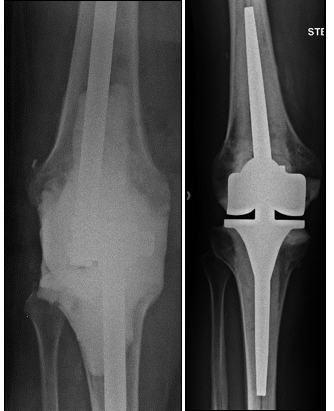

Abbildung 1 a–b:

a) Schematische Darstellung des Kniegelenkes (Fa. Aesculap)

b) Arthrose mit aufgefasertem Gelenkknorpel am Oberschenkel (Pathologisches Institut der Charité Berlin)